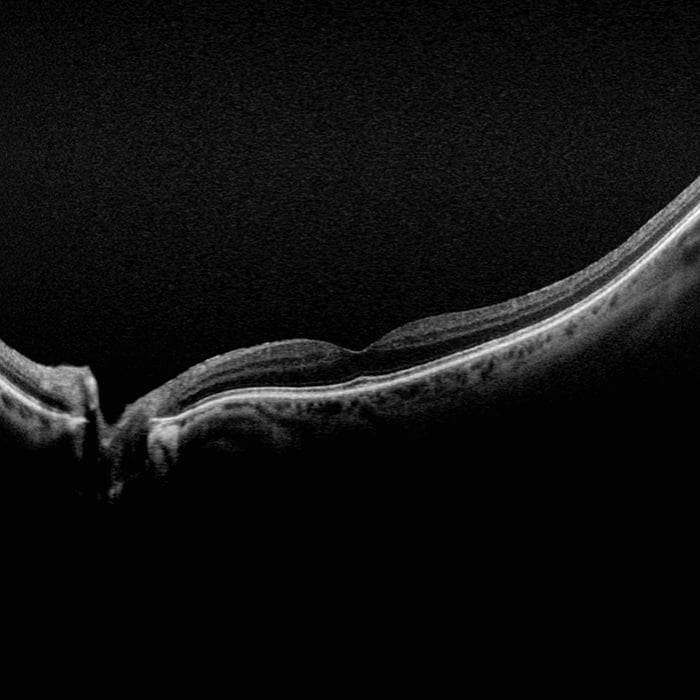

Silverstone RGB is redefining excellence in retinal imaging. It is the only device that captures true color, 200° optomap ultra-widefield images in a single shot, seamlessly integrated with guided swept-source OCT. For the first time, eye care professionals can access nine powerful imaging modalities in one system, each designed to image pathology anywhere in the retina.

optomap has been shown to enhance pathology detection, disease management, and to improve clinic flow. Now with nine retinal imaging modalities, including integrated, peripheral Swept Source OCT, Silverstone RGB facilitates examination of the retina from vitreous through the choroidal-scleral interface.

- OCT: Up to 23mm line scan and swept-source functionality